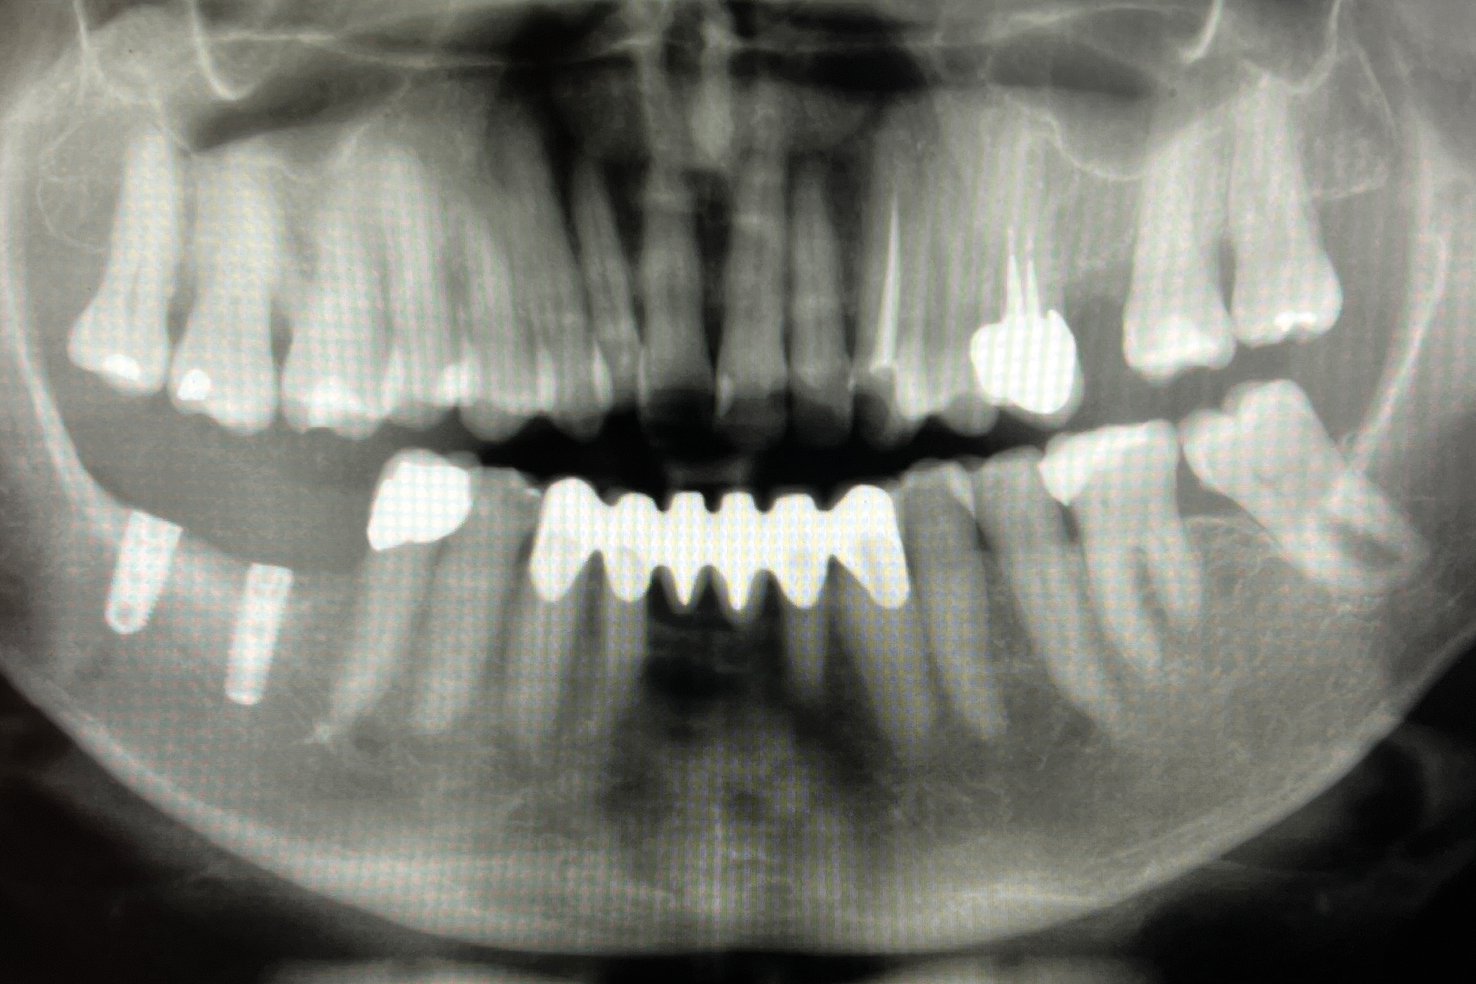

Fig 12. Radiograph and drawing of the mandibular canal.

Figure 12

Patient 2, a 50-year-old woman with minor osteoporosis, needed grafting because of  severe atrophy in the right mandible (Siebert class II) (Figure 11 and Figure 12). The  titanium mesh mesh was designed using CAD/CAM tech- nology in the same manner as in Case I. In this case, a mix of autologous and xeno- graft was used. Re-entry time was 8 months. The same protocol was followed as in Case 1 (Figure 13 through Figure 17).